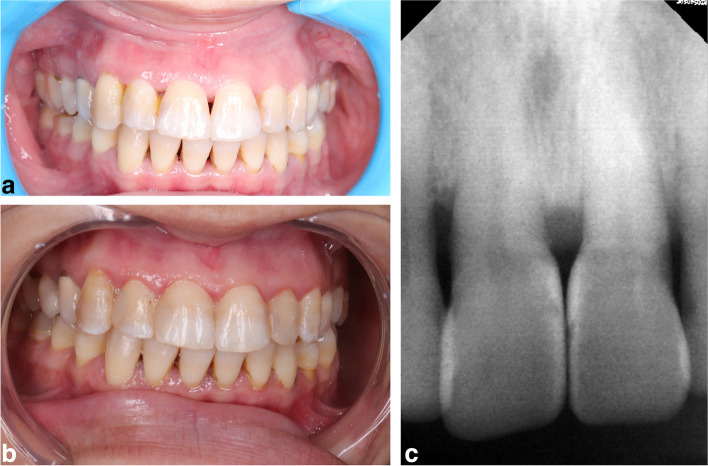

Fig. 5.

a epresentative preoperative photograph for black triangle between maxillary central incisors for bioclear matrix group. b representative postoperative photograph for black triangle between maxillary central incisors for bioclear matrix group after one year follow up period. c representative postoperative radiograph for black triangle between maxillary central incisors for bioclear matrix group after one year follow up

Fig. 6.

a Representative preoperative photograph for black triangle between maxillary central incisors for conventional celluloid matrix group. b representative postoperative photograph for black triangle between maxillary central incisors for conventional celluloid matrix group after one year follow up. c representative postoperative radiograph for black triangle between maxillary central incisors for conventional celluloid matrix group after one year follow up